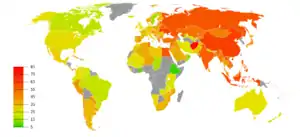

Usage

Though tobacco may be consumed by either smoking or other smokeless methods such as chewing, the World Health Organization (WHO) only collects data on smoked tobacco.[1] Smoking has therefore been studied more extensively than any other form of tobacco consumption.[2]

In 2000, smoking was practiced by 1.22 billion people, predicted to rise to 1.45 billion people in 2010 and 1.5 to 1.9 billion by 2025. If prevalence had decreased by 2% a year since 2000 this figure would have been 1.3 billion in 2010 and 2025.[290] Despite dropping by 0.4 percent from 2009 to 2010, the United States still reports an average of 17.9 percent usage.[61]

The WHO states that "Much of the disease burden and premature mortality attributable to tobacco use disproportionately affect the poor". Of the 1.22 billion smokers, 1 billion live in developing or transitional nations. Rates of smoking have leveled off or declined in the developed world.[294] In the developing world, however, smoking rates were rising by 3.4% per year as of 2002.[291]

The WHO in 2004 projected 58.8 million deaths to occur globally,[295]: 8 from which 5.4 million are smoking-attributed,[295]: 23 and 4.9 million as of 2007.[296] As of 2002, 70% of the deaths are in developing countries.[296]

The shift in prevalence of tobacco smoking to a younger demographic, mainly in the developing world, can be attributed to several factors. The tobacco industry spends up to $12.5 billion annually on advertising, which is increasingly geared towards adolescents in the developing world because they are a vulnerable audience for the marketing campaigns. Adolescents have more difficulty understanding the long-term health risks that are associated with smoking and are also more easily influenced by "images of romance, success, sophistication, popularity, and adventure which advertising suggests they could achieve through the consumption of cigarettes". This shift in marketing towards adolescents and even children in the tobacco industry is debilitating to organizations' and countries' efforts to improve child health and mortality in the developing world. It reverses or halts the effects of the work that has been done to improve health care in these countries, and although smoking is deemed as a "voluntary" health risk, the marketing of tobacco towards very impressionable adolescents in the developing world makes it less of a voluntary action and more of an inevitable shift.[4]